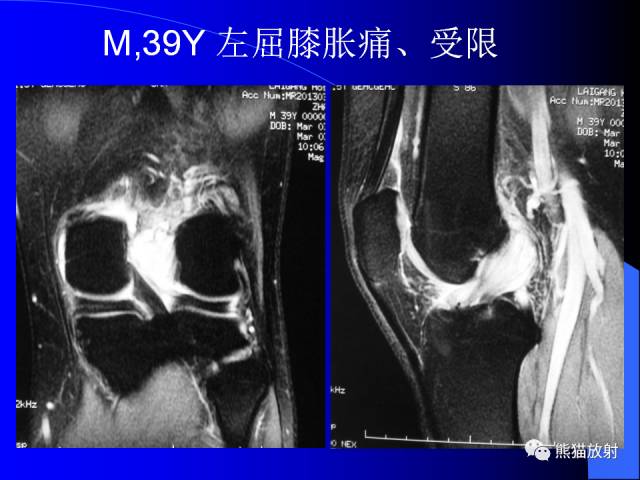

膝关节周围囊肿是较常见的病变,可以是原发的,多见于青年及儿童,囊内容物通常是黏液;也可以是继发的,多与关节腔相通,内含一般黏性的滑液,常继发于膝关节骨关节炎、类风湿关节炎、非特异性滑膜炎、半月板损伤、髌骨软骨软化症等。

腘窝囊肿是膝关节周围最常见的囊肿。